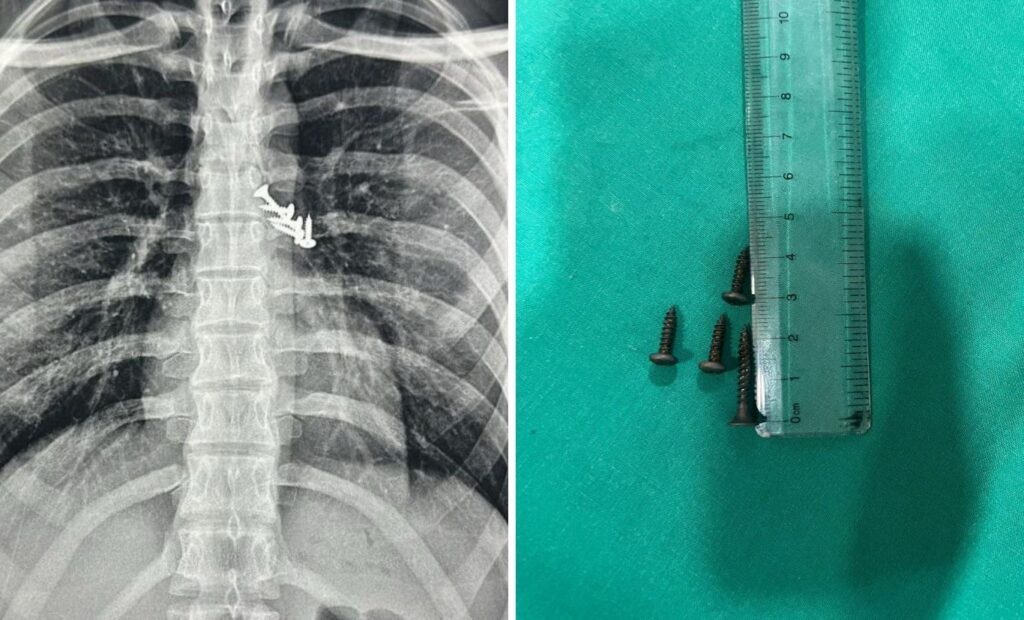

Pune: Doctors Save Life of 19-Year-Old Electrician After Removing 7 Nails from Lungs and Stomach

In a rare and life-saving medical intervention, surgeons at Dr. D.Y. Patil Hospital in Pimpri successfully removed seven sharp nails from a 19-year-old electrician’s body, five from his lungs and two from his stomach, after a workplace accident. The young worker had been installing aluminium sheets for a false ceiling when he accidentally stepped on an exposed […]